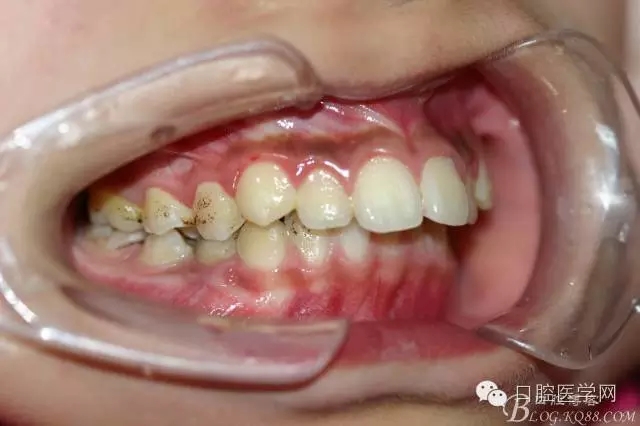

正畸查:替牙合。第一恒磨牙中性合。上牙弓尖圓型下牙弓方圓型。前牙覆合3度覆蓋7.5mm。下前牙咬到上舌側(cè)牙齦。上頜擁擠4.0mm,下頜擁擠

3.0mm。上頜稍前突下頜后縮,上下唇前突,上前牙覆蓋下唇,下唇外翻。面下三分之一過短,頦唇溝明顯,開唇露齒,頦饜窩明顯。顳下頜關(guān)節(jié)開閉口無彈響,無壓痛,開口型開口度正常。

正畸前照片: